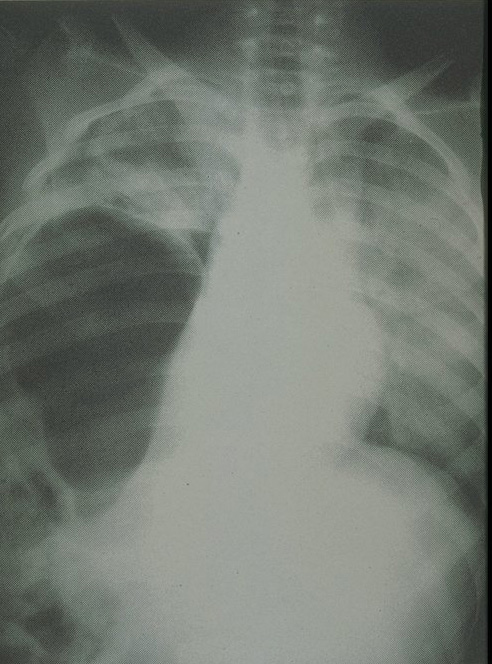

Multiple thoracoabdominal injury, haziness and blunting of costodiaphragmatic recess indicating the hemothorax.

Plain chest X-ray finding of ruptured diaphragm. The bowel gas pattern is noted in the right hemithorax